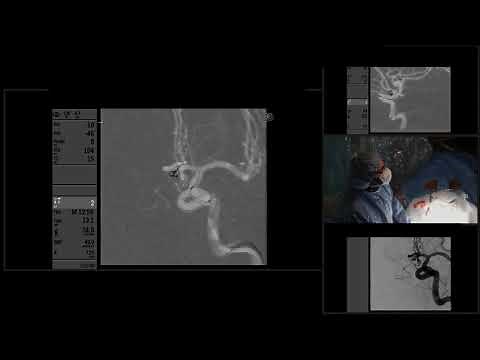

Procedure - Coiling

Coiling - Endovascular Coiling

for Brain Aneurysms - Aneurysm Clipping